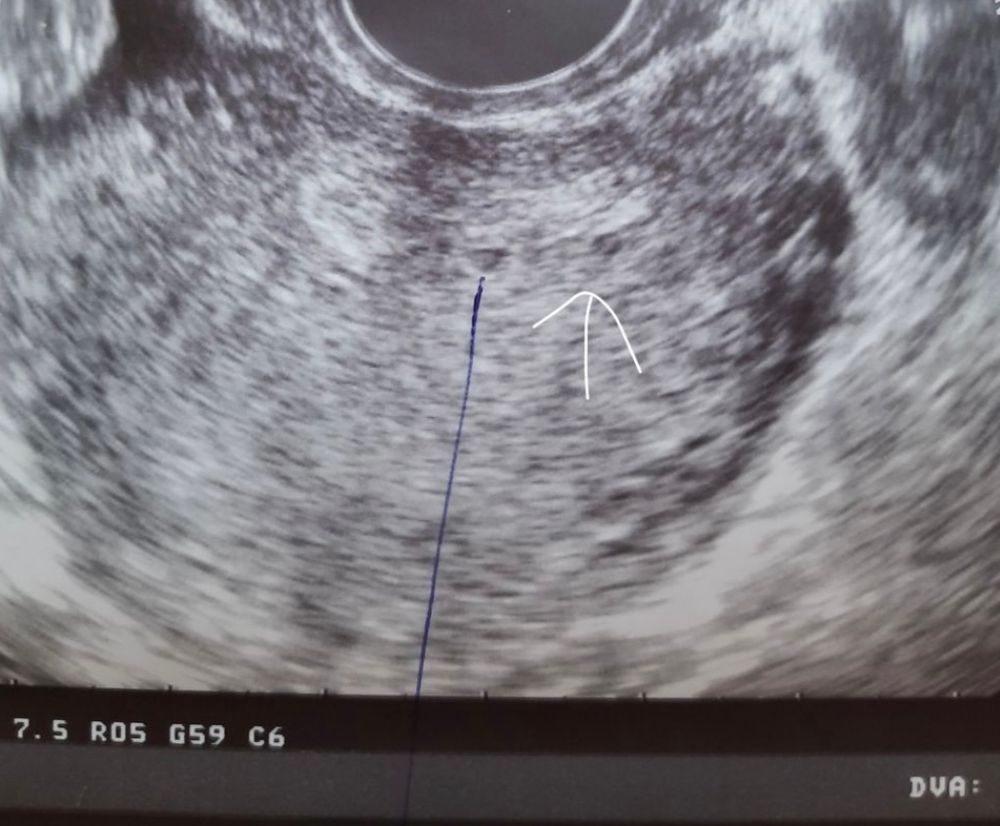

Склонность к двойне☺️

Anastasiya, это со вторым сыном было)где то на 3-4 д.з)

ViksikKash , это старый снимок с младшим сыном🥰У меня могло бы быть уже 3 е деток,но второй замер((

Моя коллекция😁 Стеноз ,трахеит